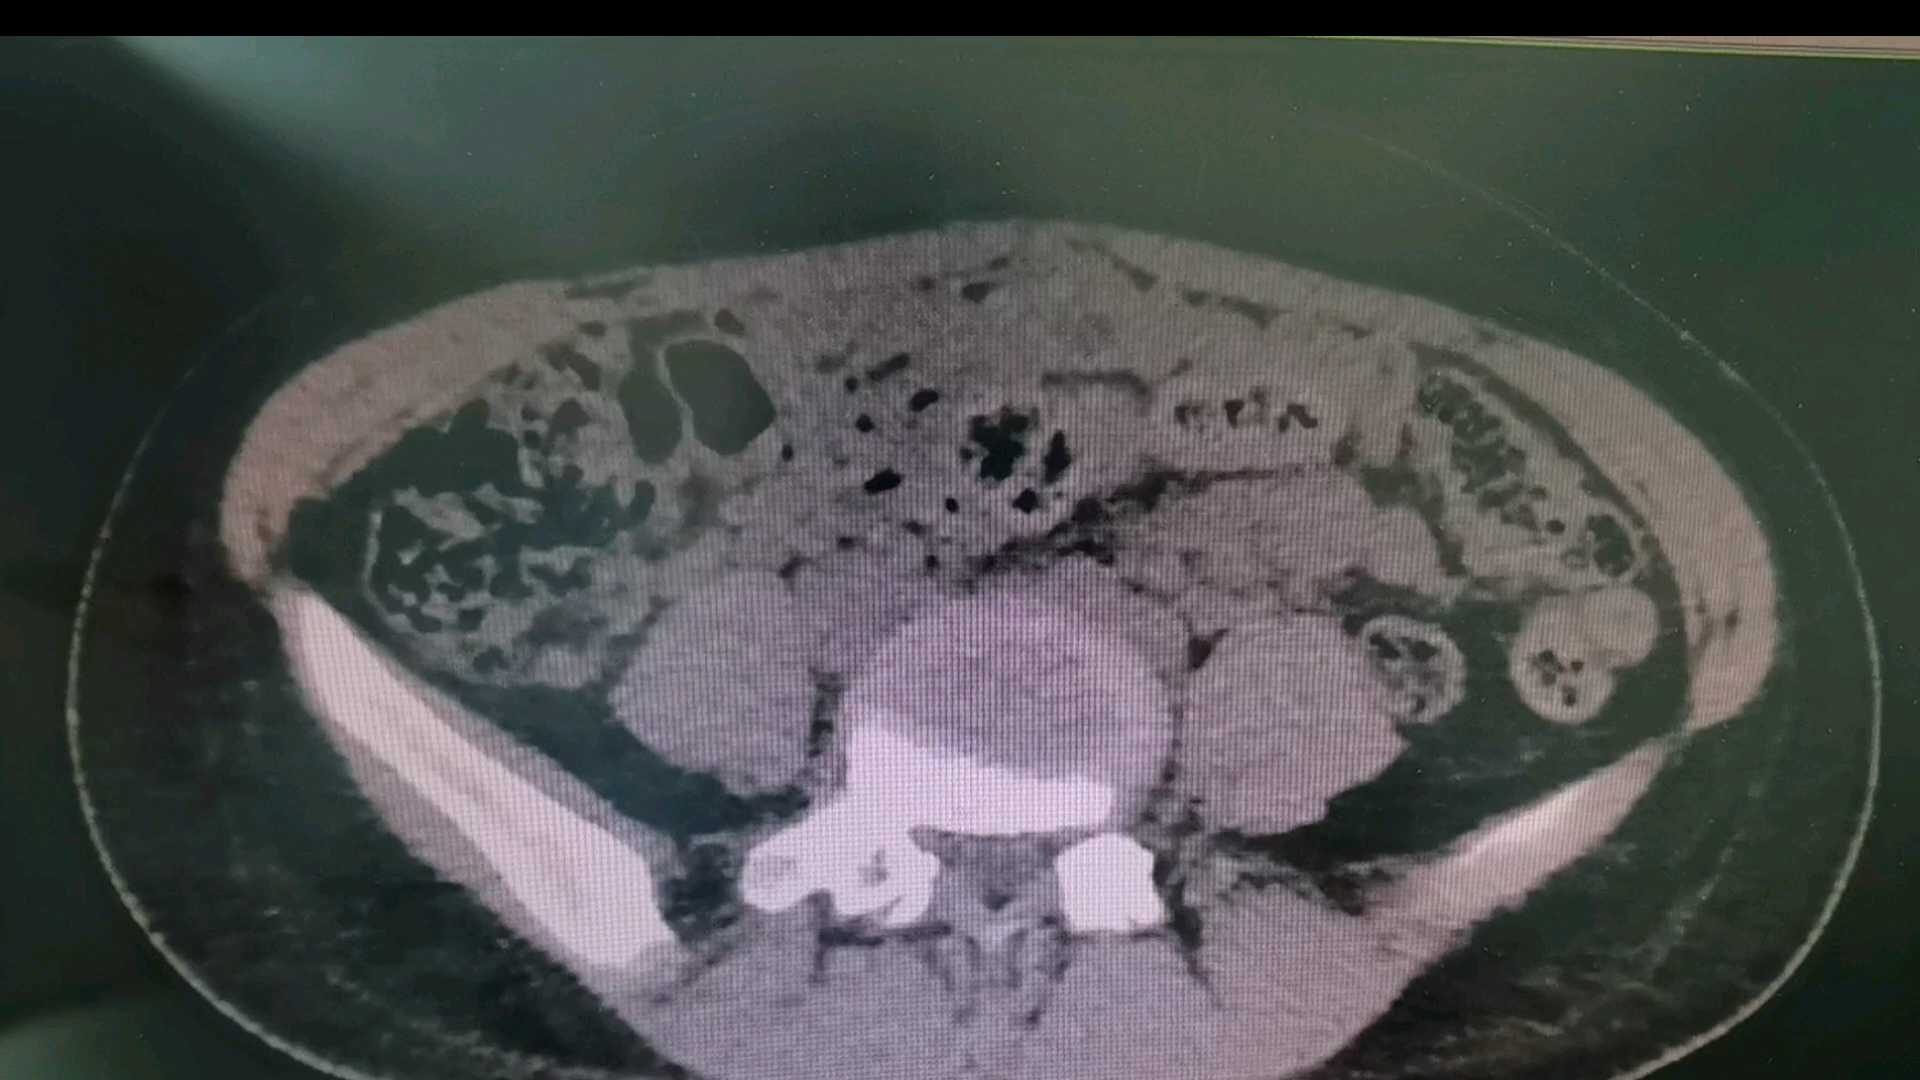

这是我一个同行朋友跟我讲的一个事,13岁女孩在父母陪同下来院就诊,主诉反复下腹部疼痛2月余,也不知道急诊医生有没有完善病史采集或者进行查体,也没有开具彩超、HCG检查,直接开具了下腹部+盆腔CT检查,CT一扫出来图像,吓得一众人脸色煞白,赶紧就报告上级领导并报了警。